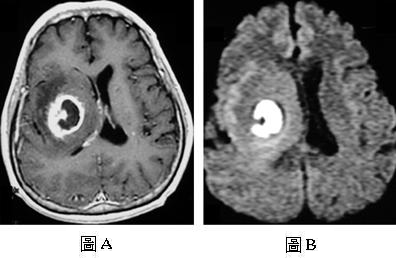

50歲男性患者,主訴左側肢體無力已經二個星期,接受磁振造影檢查,圖A是注射顯影劑後的T1加權影像,圖B是擴散加權影像(diffusion-weighted image),下列何者是最可能的診斷?